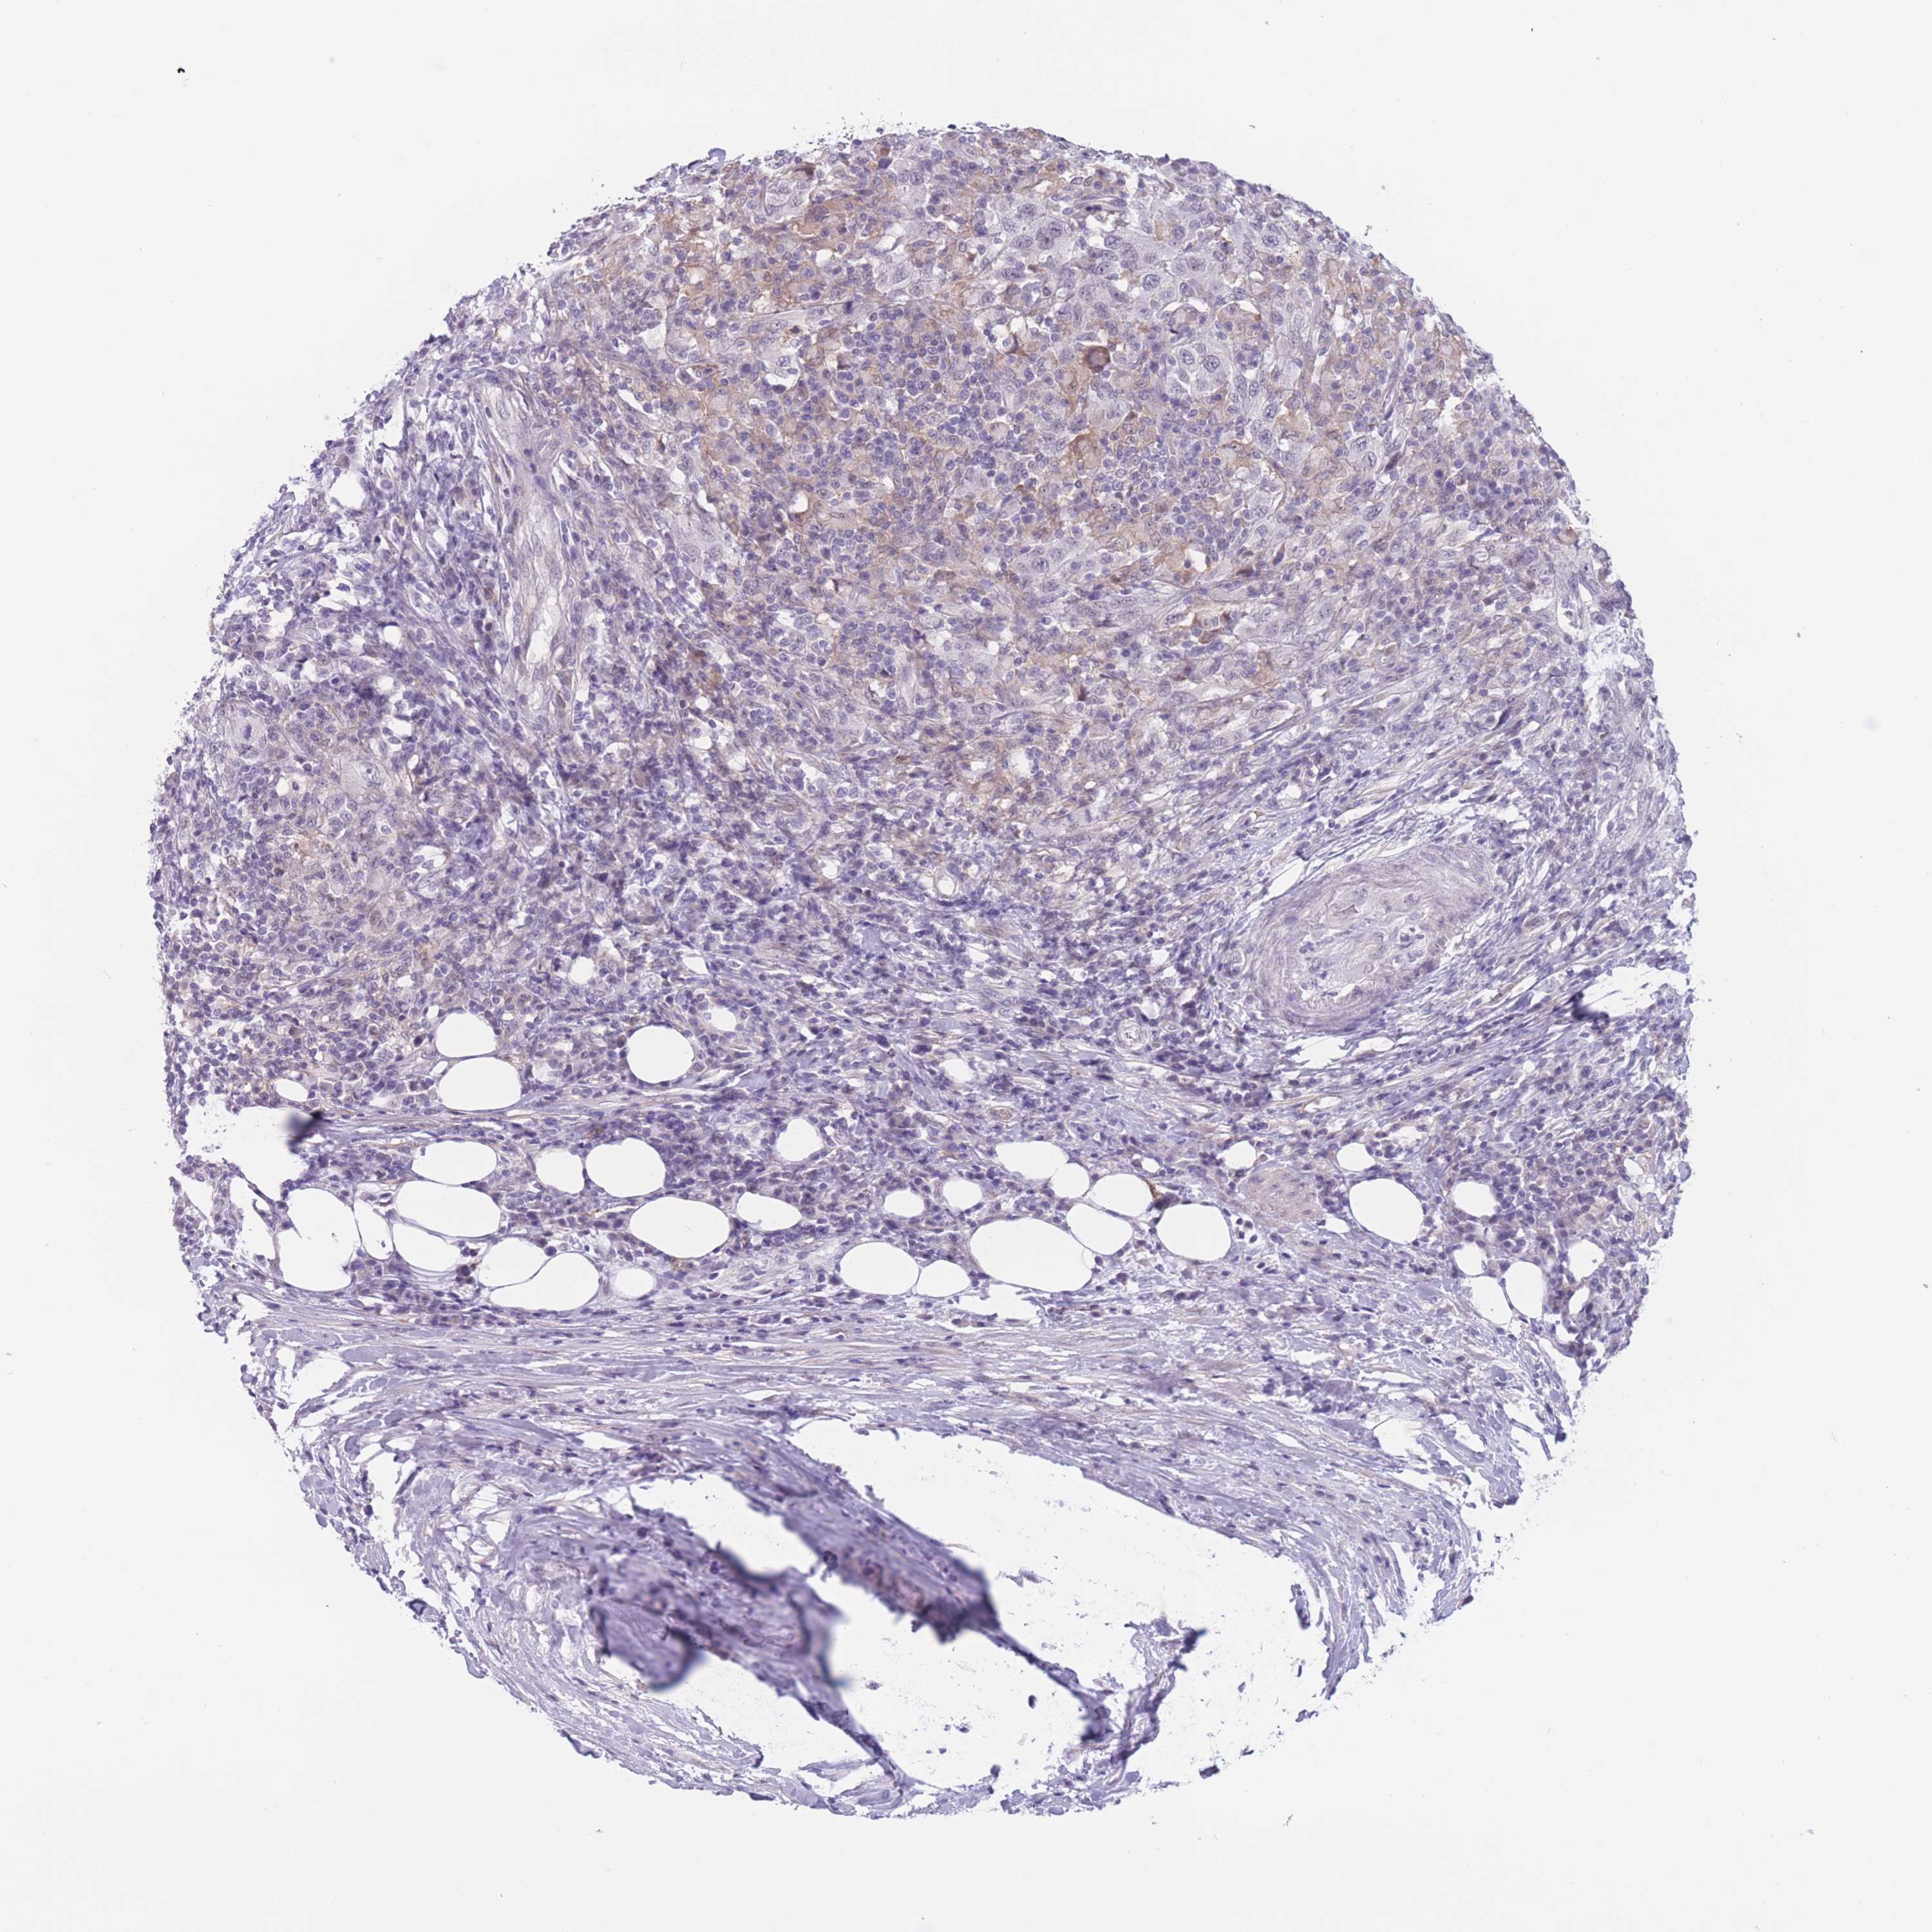

UROTHELIAL CANCER - Protein expressioni

A mouse-over function shows sample information and annotation data. Click on an image to view it in a full screen mode. Samples can be filtered based on level of antibody staining by selecting one or several of the following categories: high, medium, low and not detected. The assay and annotation is described here.

Note that samples used for immunohistochemistry by the Human Protein Atlas do not correspond to samples in the TCGA dataset.

Antibody stainingi

Antibody staining in the annotated cell types in the current human tissue is reported as not detected, low, medium, or high, based on conventional immunohistochemistry profiling in selected tissues. This score is based on the combination of the staining intensity and fraction of stained cells.

Each image is clickable and will lead to virtual microscopy that enables deeper exploration of all samples and also displays staining intensity scores, fraction scores and subcellular localization as well as patient and tissue information for each sample.

HPA002110

HPA045507

CAB016169

CAB062558

CAB068219

CAB068220

Staining

High

Medium

Low

Not detected

Intensity

Strong

Moderate

Weak

Negative

Quantity

>75%

75%-25%

<25%

None

Location

Nuclear

Cytoplasmic/membranous

Cytoplasmic/membranous,nuclear

Urothelial carcinoma, High grade

Urothelial carcinoma, NOS

Urothelial carcinoma, Low grade